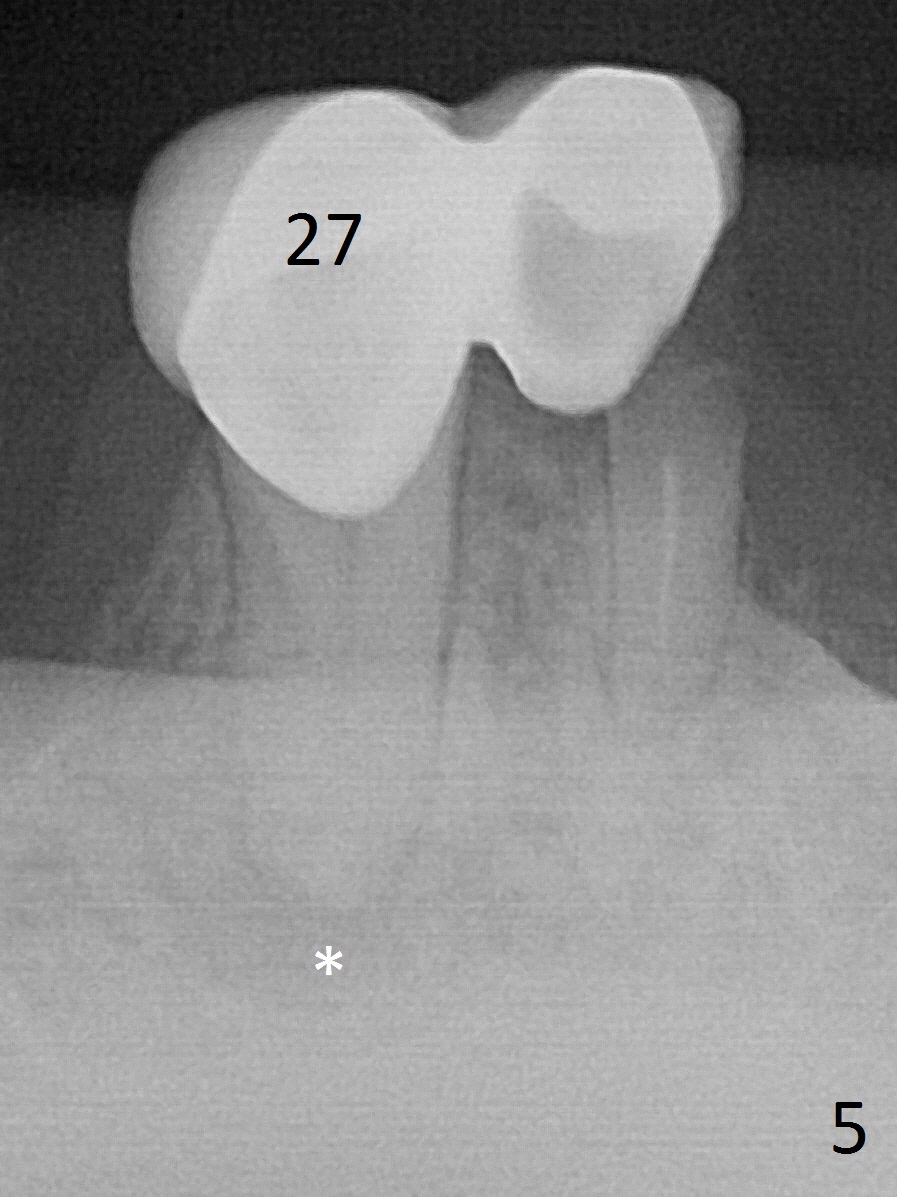

A 62-year-old woman has poor dentition (Fig.1). The most critical area is the upper left anterior: #9-11, which were extracted 4 months earlier (Fig.2). Implants will be placed at #9 and 11 with fabrication of a provisional bridge (Fig.3). After incision, use Magic Split to start bone expansion, followed by micro-osteotomes 1 and 1.5 mm and Magic Osteotomes 3 and 3.8 mm. If the transition between 1.5 and 3 mm osteotomes is not smooth, apply RT2. Place the smallest bone-level implants (for hybrid denture in the future) with gold coated abutments. There should be no interference with or without the partials and in and out. Next step should be removing splinted crowns at #26 and 27 (Fig.1), RCT for #27 and immediate implant at #26 (Fig.5,6 Metronidazole). In fact the splinted crowns at #26 and 27 were lost last week. The patient thinks that she needs 2 implants. The next one is to remove the crown at #5 for RCT (Fig.4).